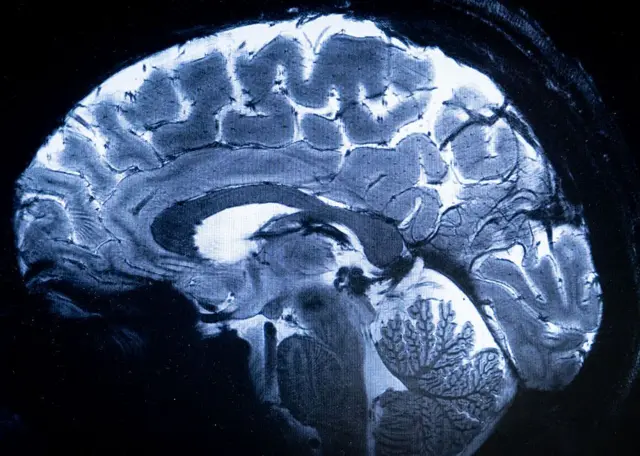

Otak melalui lima fase berbeda dalam kehidupan. Adapun titik balik penting terjadi pada usia sembilan, 32, 66, dan 83 tahun, ungkap sejumlah ilmuwan.

Dalam penelitian Universitas Cambridge, sekitar 4.000 orang berusia anak-anak hingga usia 90 tahun menjalani pemindaian untuk mengungkap hubungan antarsel otak mereka.

Otak terus berubah guna merespons pengetahuan dan pengalaman baru. Namun, penelitian menunjukkan bahwa ini bukanlah pola yang mulus dari lahir hingga mati.

Terdapat lima tahap perkembangan otak, menurut penelitian tersebut.